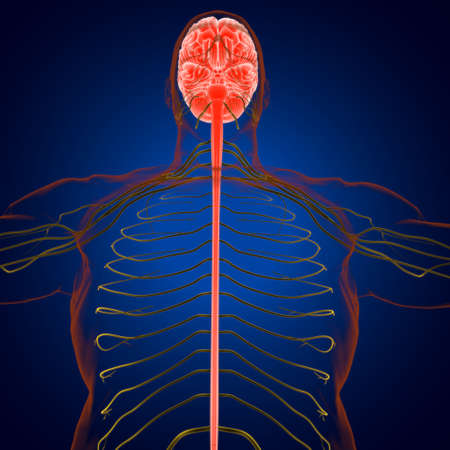

3D Illustration Concept of Central Organ of Human Nervous System Brain Anatomy

Illustrating the role of the central nervous system in processing sensory information and coordinating motor responses.

A captivating digital depiction of the human nervous system, highlighting the brain and spinal cord with glowing neural connections, perfect for educational materials.

Detailed anatomical illustration showing the human brain, spine, and nervous system with a focus on the intricate connections between them

An Electro stimulation digital illustration of human nervous system, highlighting brain and spinal cord with glowing nerve pathways